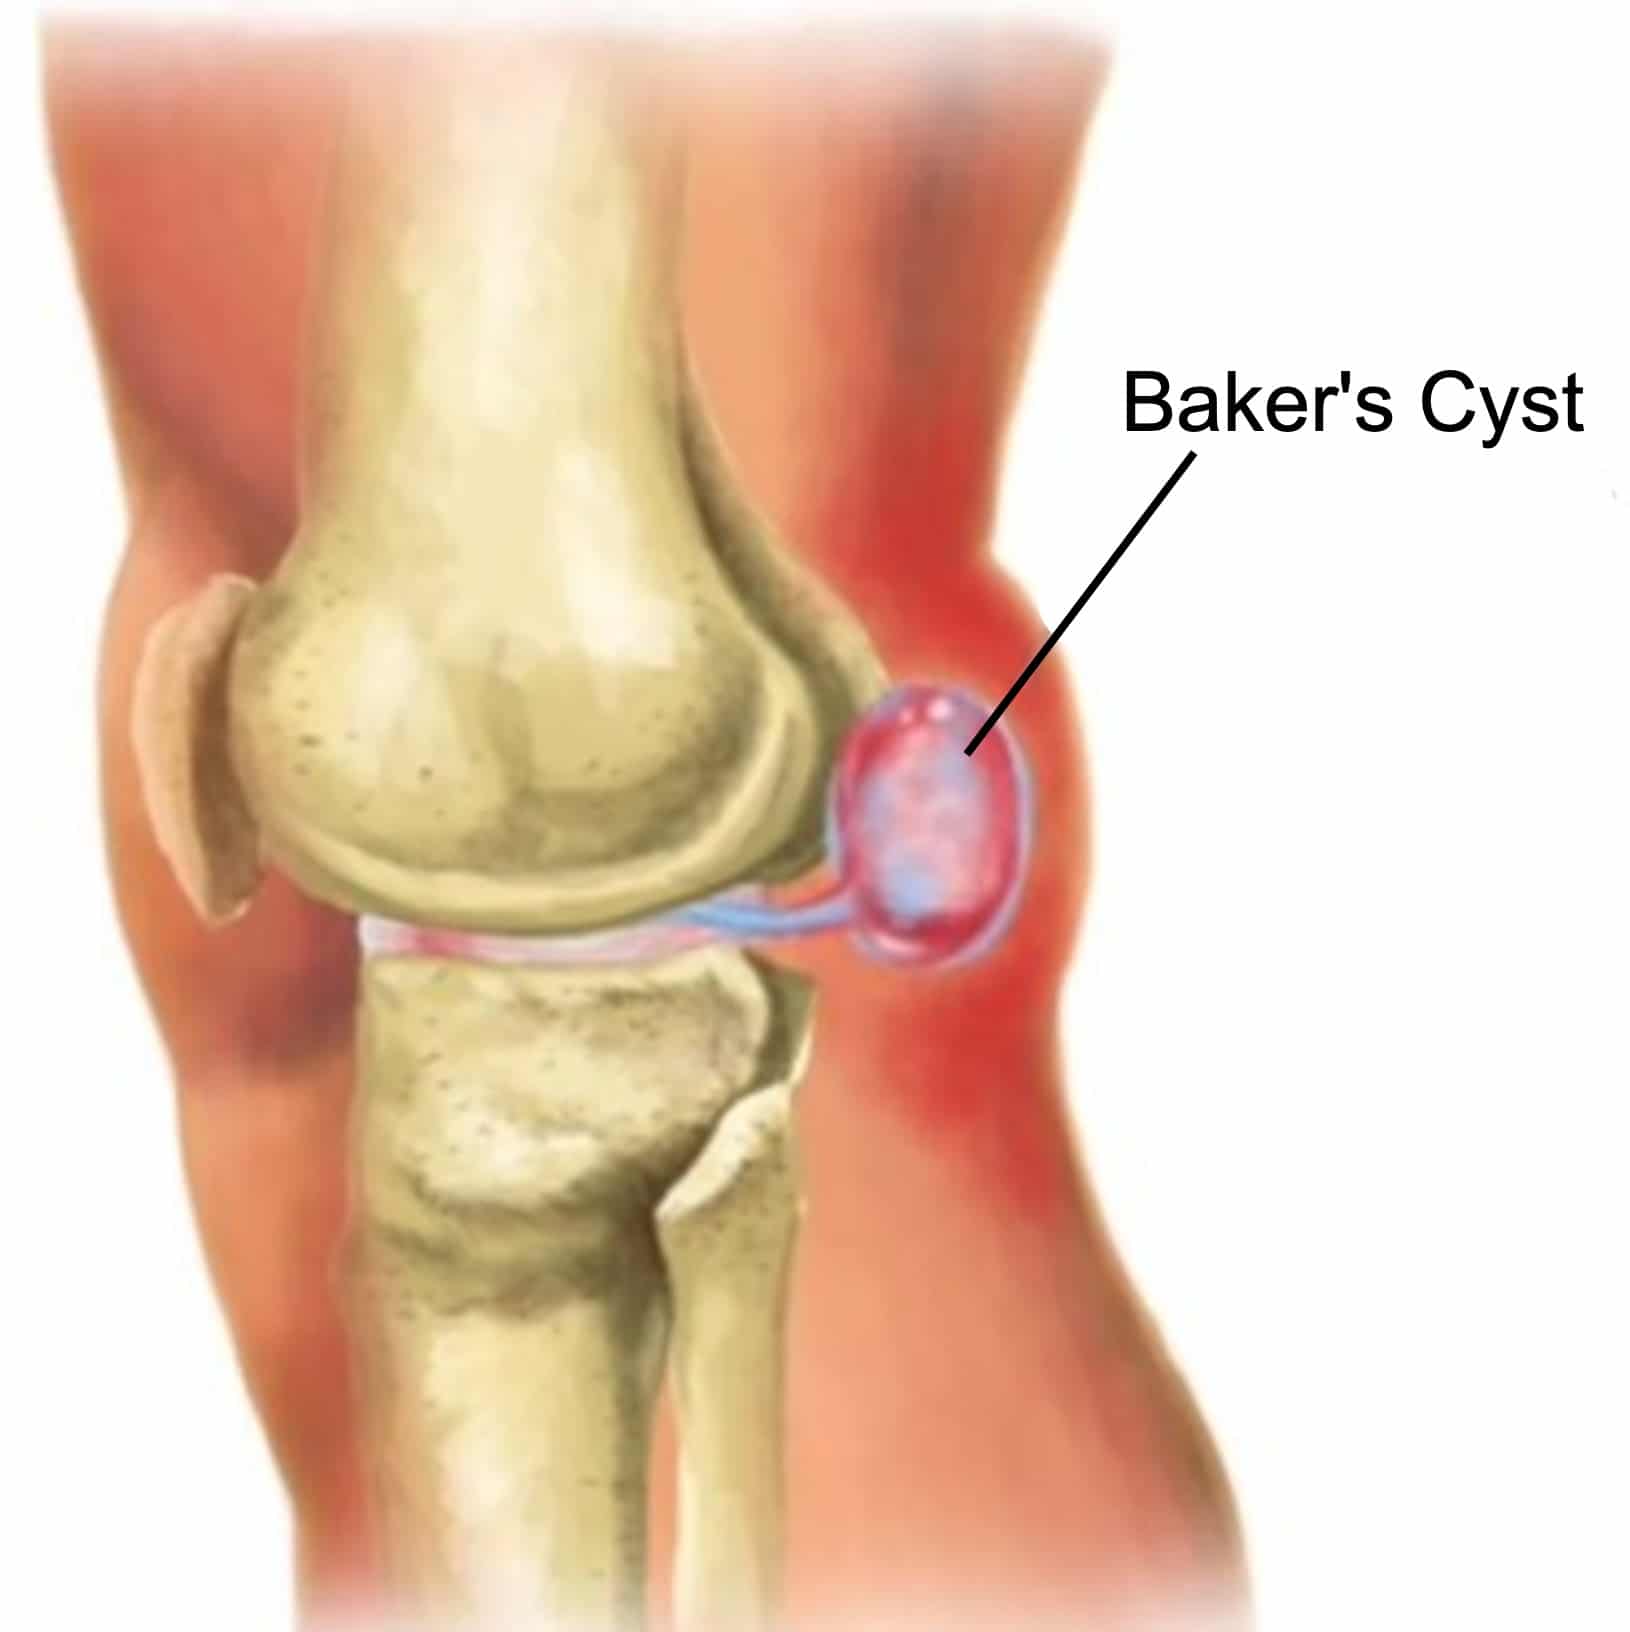

Фото и диагностика кисты Бейкера